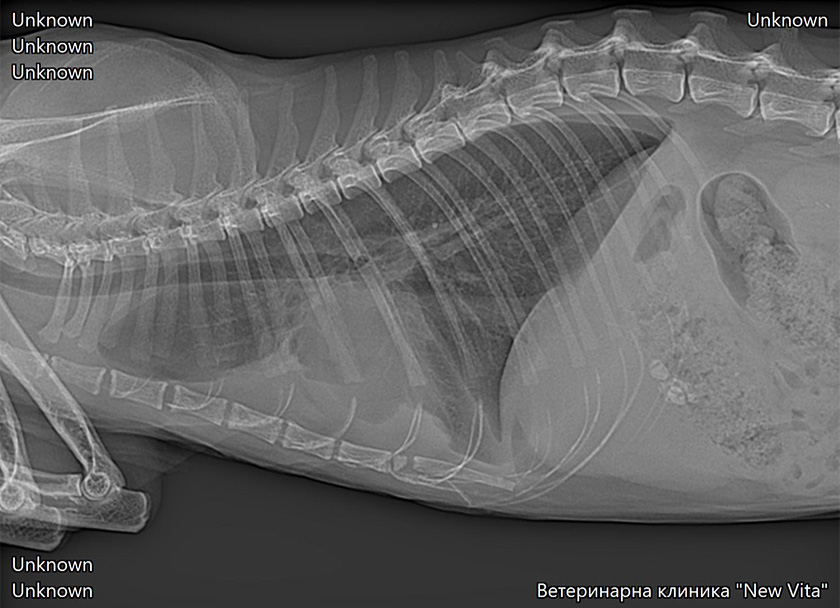

Най-честата рентгенологична находка при котки със сърдечни проблеми е наличието на плеврален излив, оток на белия дроб, Увеличени белодробни съдове, увеличен сърдечен силует-кардиомегалия (не е задължително да се установи, за да бъде поставена диагнозата, много често сърцето е външни размери). Процедурата по получаване на качествени и диагностични рентгенологични снимки може да бъде отложена докато пациента не бъде стабилизиран. Изискват се минимум две рентгенови снимки в две проекции.

Това са рентгенови снимки на наши пациенти. Те показват наличие на плеврален излив и оток на белия дроб.